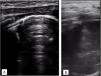

The chest radiograph showed complete opacity of the right upper lobe (Fig. 1), while the findings of serial lung ultrasound scans were normal (Fig. 2A). The chest ultrasound examination with a supraclavicular approach showed a well-defined area of consolidation suggestive of a thoracic mass (Fig. 2B and Appendix B, Video 1), which was corroborated in the CT scan (Fig. 3). Examination of a biopsy specimen confirmed the diagnosis of congenital neuroblastoma.

Chest ultrasound scan performed with a high-frequency linear transducer. (A) Longitudinal scan at the level of the anterior lung fields. Adequate lung sliding, normal aeration in every lung field, with presence of A-lines and a lung ultrasound score of zero. (B) Right supraclavicular fossa view. Consolidation without air bronchogram or contrast enhancement on Doppler with a well-demarcated, deep and round border and a maximum diameter of 6cm.